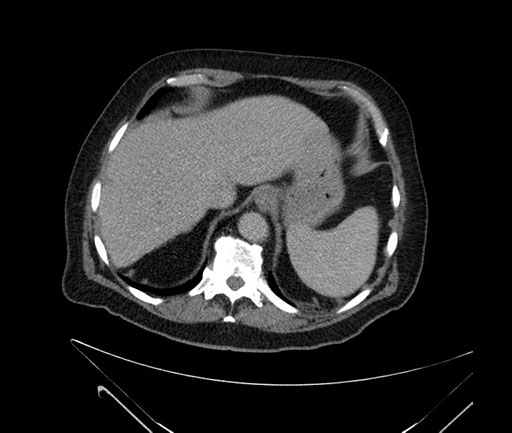

Axial - 3 months prior